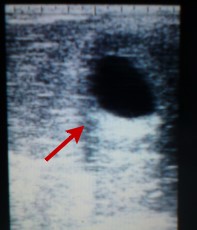

... nachdem Nele es schon aufgrund der Charakterveränderung von Maus vermutet hatte,  aber nicht zu glauben gewagt hatte, haben wir am Dienstag endlich Gewissheit bekommen:

Maus ist in der 9. Woche schwanger !!!

Die Anpaarung mit unserem Tänzer Háfeti  ist eine Traumanpaarung von Nele,

"Mrs.  Kick it " und "Mr. Dancer".. =  " Funky junior. "

Wer die Vorgeschichte von Maus kennt, kann sich vorstellen wie sehr wir uns über dieses Ergebniss freuen und  hoffen natürlich sehr, daß wir nächstes Jahr "Funky junior"  auf der Weide bei uns begrüßen dürfen.